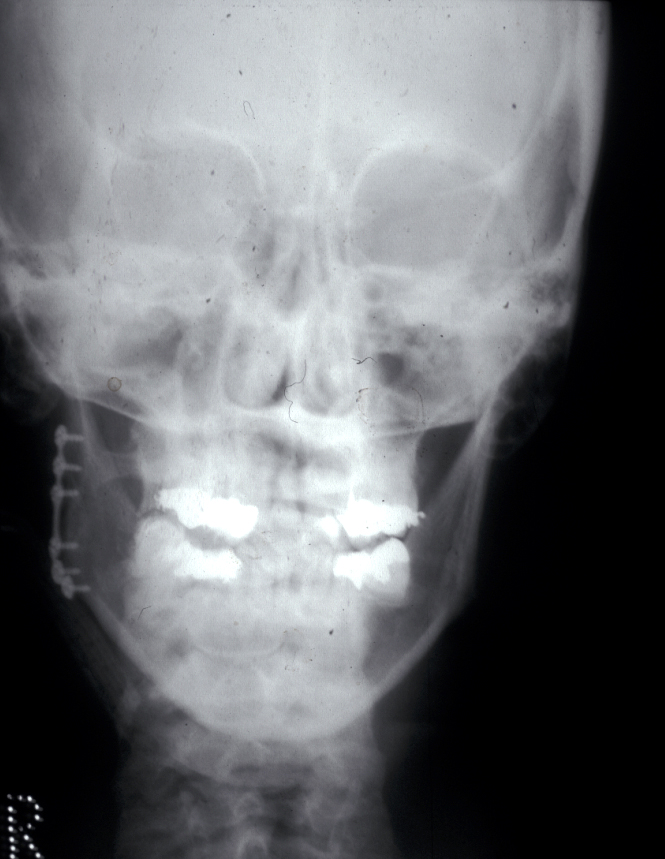

Joint replacement is a significant operation for symptomatic irreparably damaged joints. Costochondral rib graft (see Figure 7) or customised prosthetic joints are used. The unpredictability of costochondral rib (a third are stable, a third resorb and a third overgrow) and refinements to customised prostheses have moved almost all jaw joint replacement for terminal joint damage to these devices (see Figure 8).

Figure 7: Postoperative X-ray radiograph of a costochondral rib graft total condyle replacement.